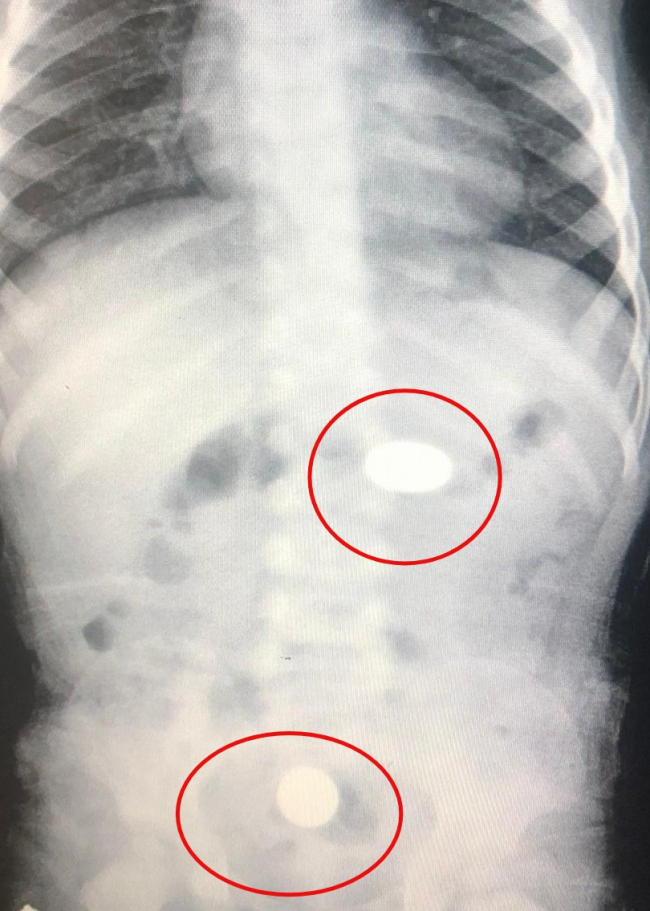

Murat bebek, İnegöl Devlet Hastanesi'ne kaldırıldı. Yapılan kontrolde paralardan birinin bebeğin midesinde, diğerinin ise yemek borusunda kaldığı tespit edildi.

Sağlık durumu iyi olan Murat bebek, paraları dışkı yoluyla atamazsa operasyona alınacak.